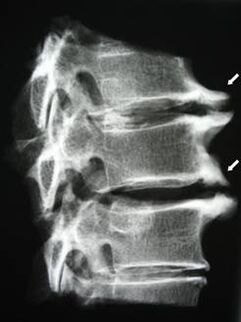

Në fazat fillestare, osteokondroza zbulohet duke përdorur MRI. Më vonë, patologjia mund të diagnostikohet duke përdorur radiografi. Në radiografitë e shtyllës kurrizore të qafës së mitrës, një ulje e distancës midis rruazave, ndryshimet patologjike në nyjet e fastës dhe osteofitoza bëhen të dukshme.